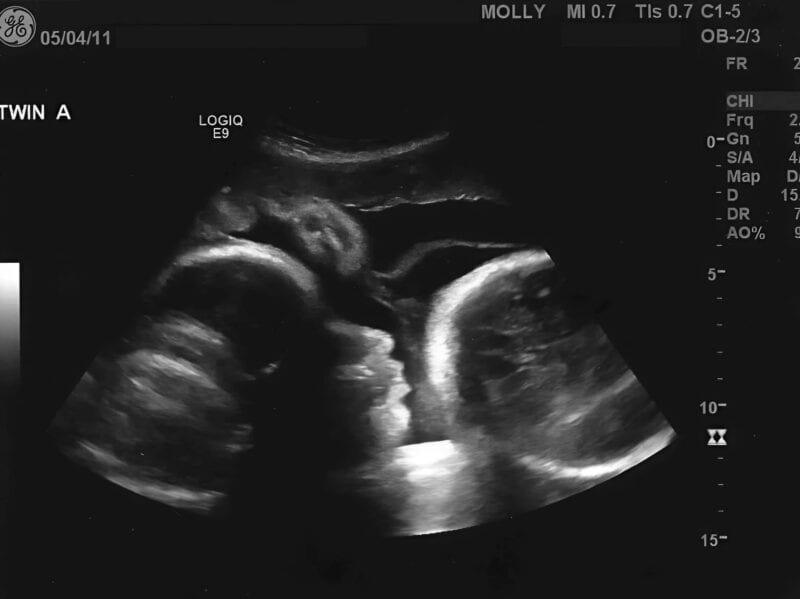

— Мэм, у вас опухоль яичника размером с доношенного младенца. Именно она росла все эти месяцы. Именно она давала ощущение «движения». И именно она — причина вашей боли. Опухоль уже дала метастазы. Это критическое состояние. Вам нужна срочная операция, химия… и времени у нас почти нет.